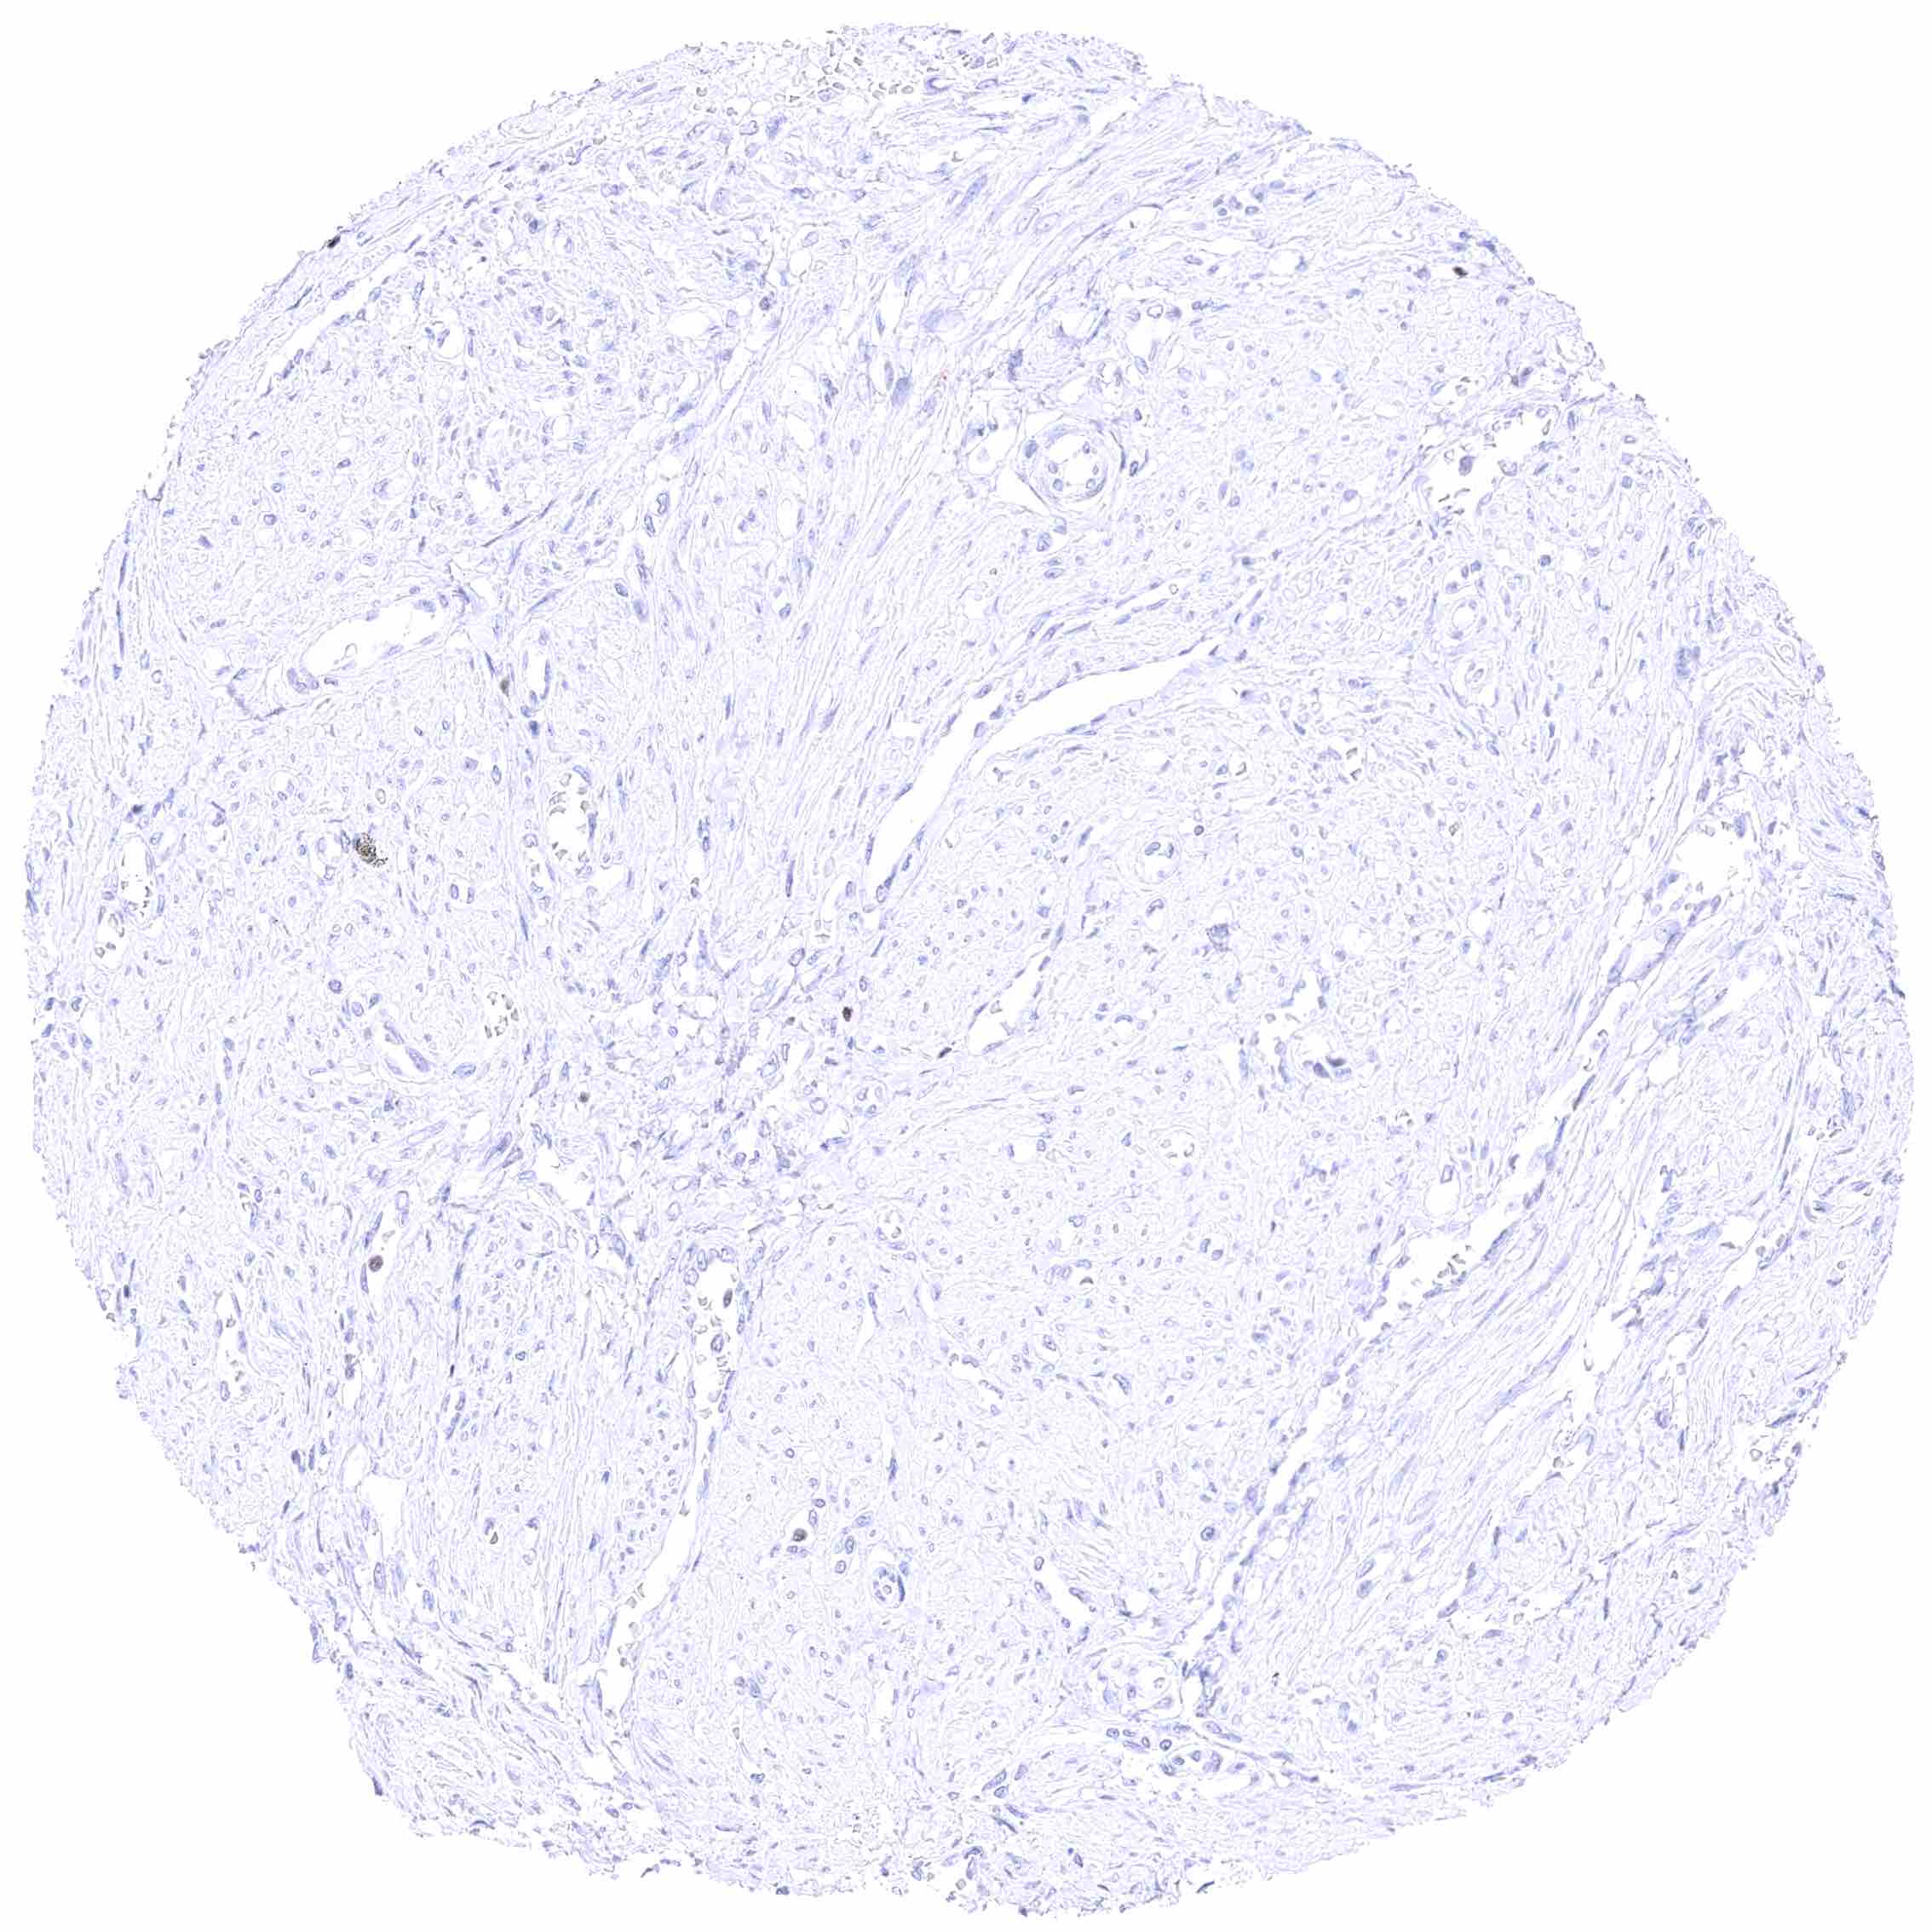

Prostate – Weak to moderate, nuclear GATA3 staining of basal cells. .jpeg